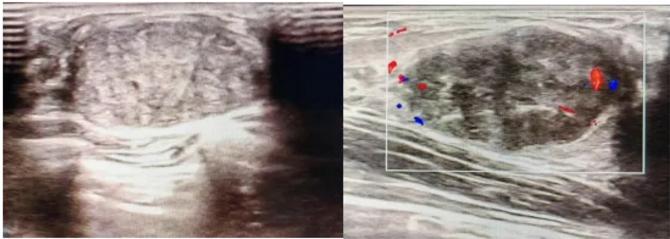

典型表現(xiàn):

橢圓形低回聲團(tuán)塊,包膜完整,內(nèi)部回聲均勻,后方回聲增強(qiáng),周邊無(wú)“蟹足樣”浸潤(rùn)。